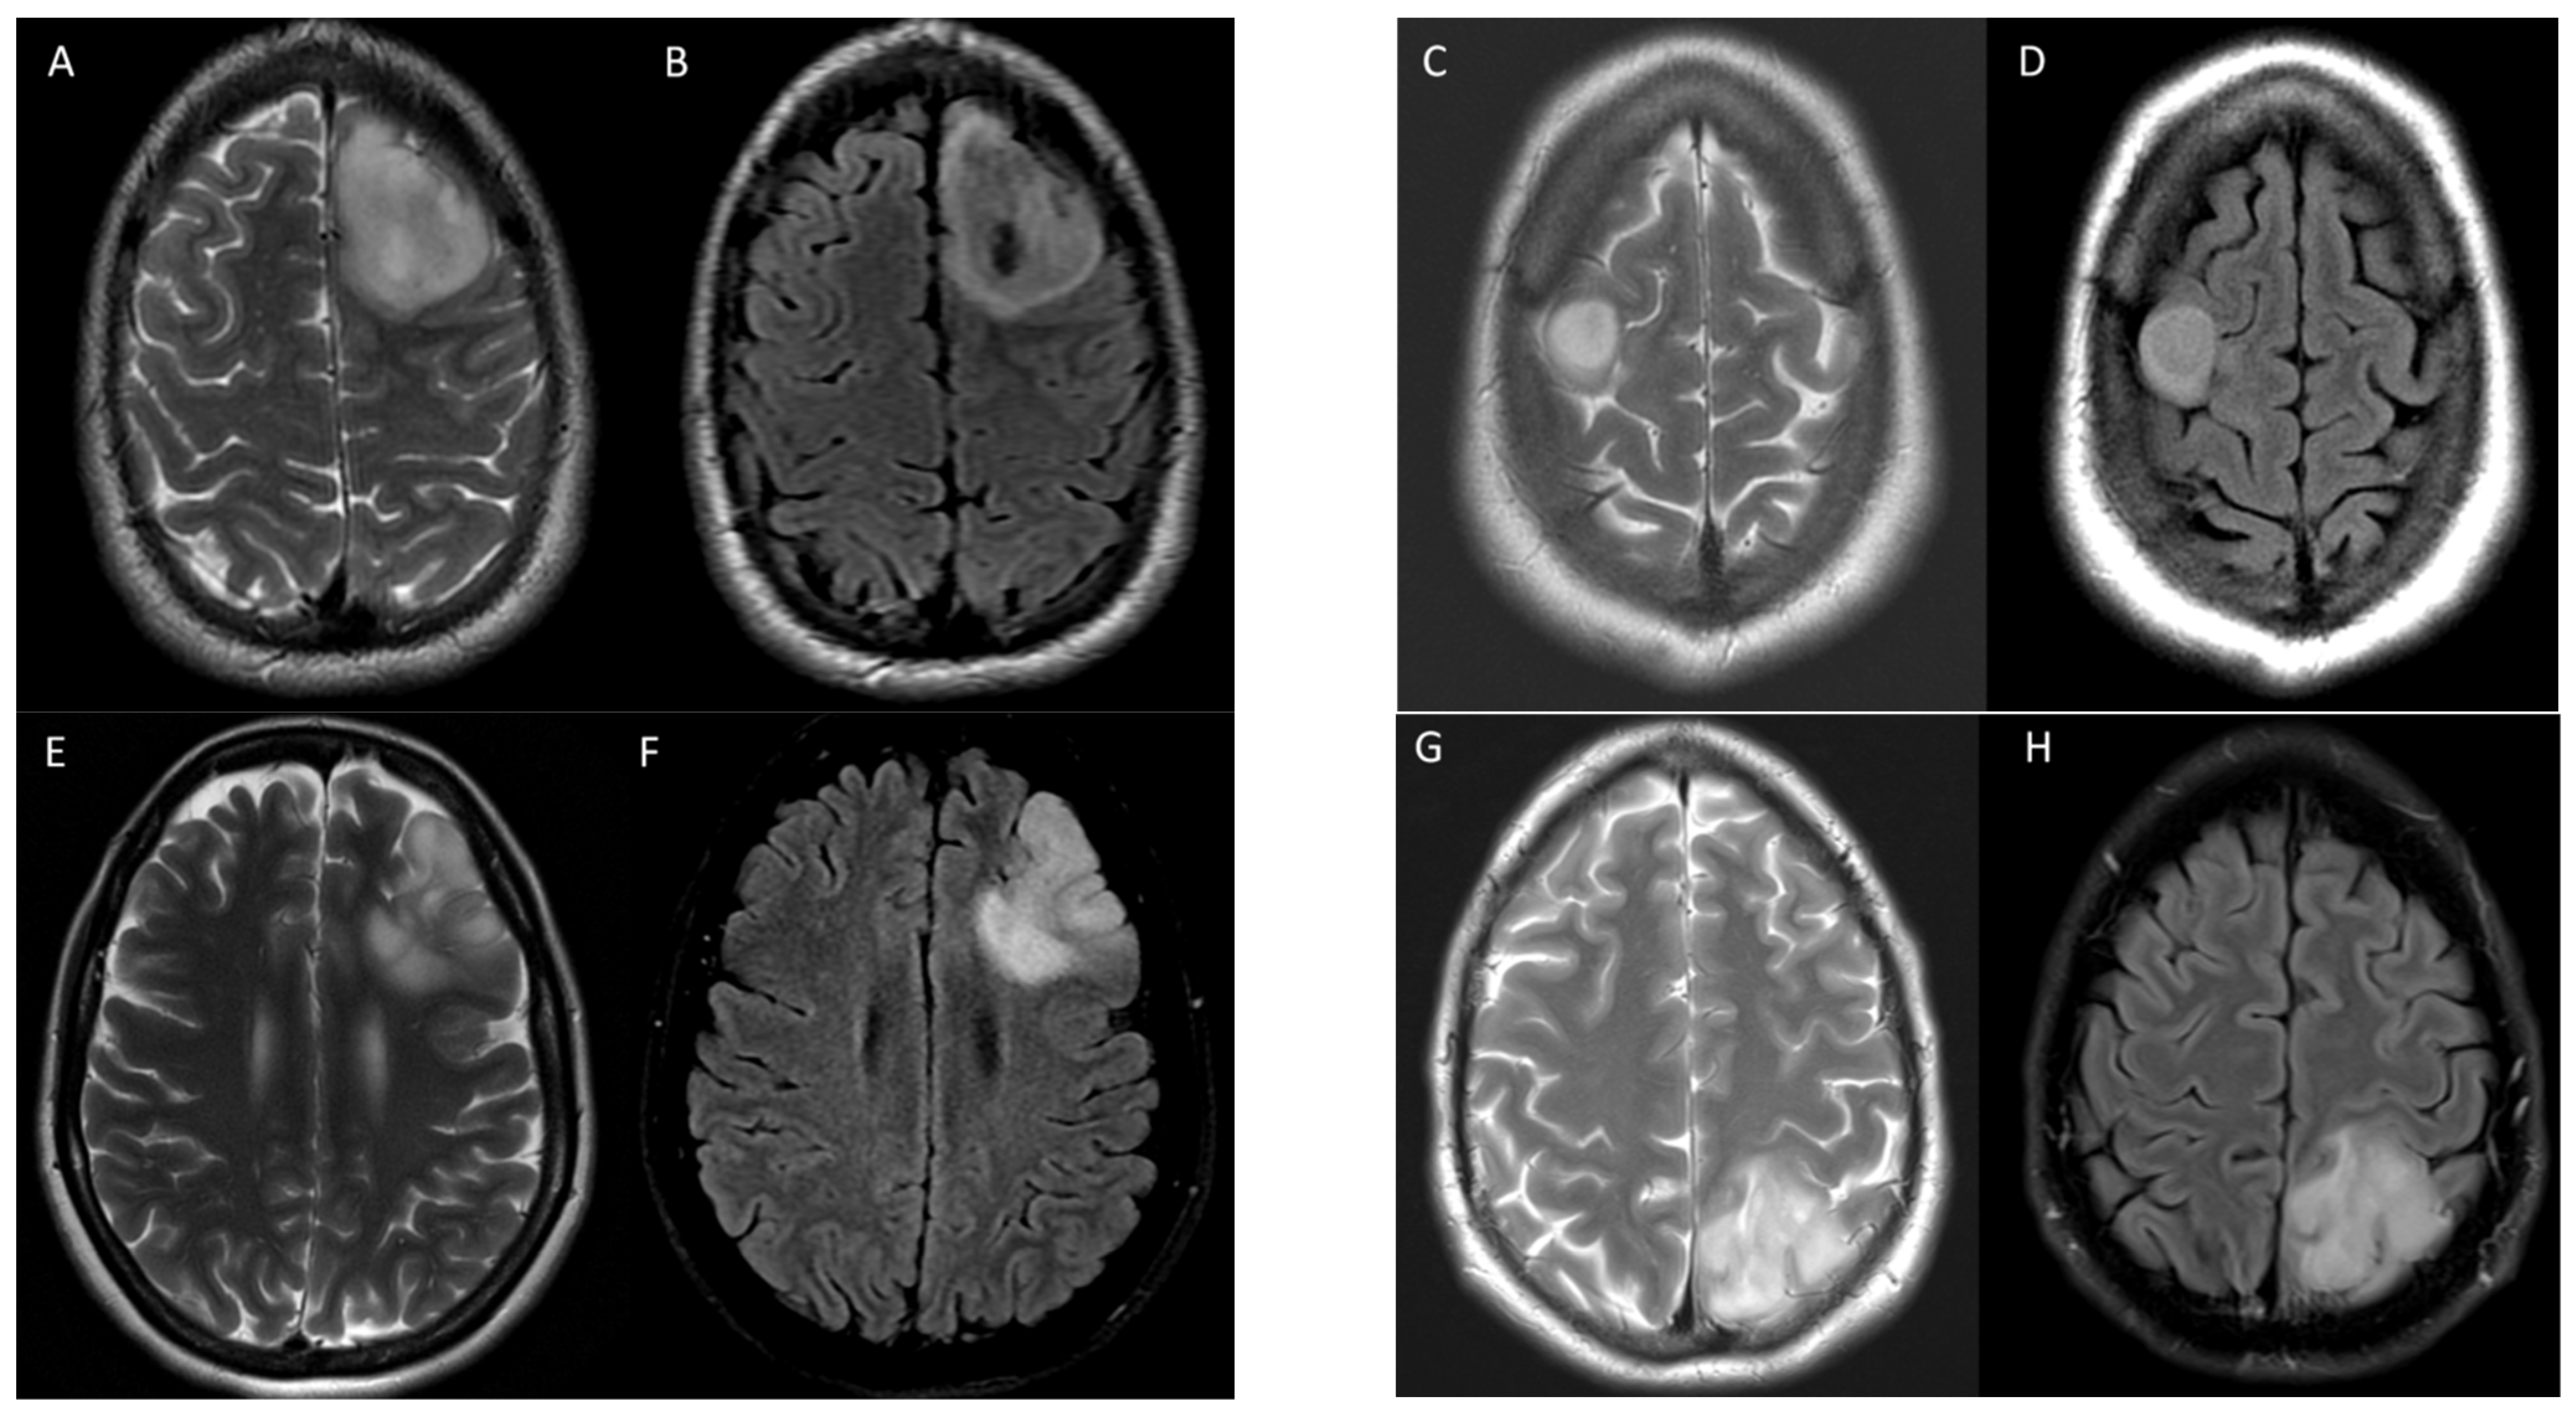

3.2. T2-FLAIR-Mismatch-Based Prediction of 1p/19q Co-Deletion Status